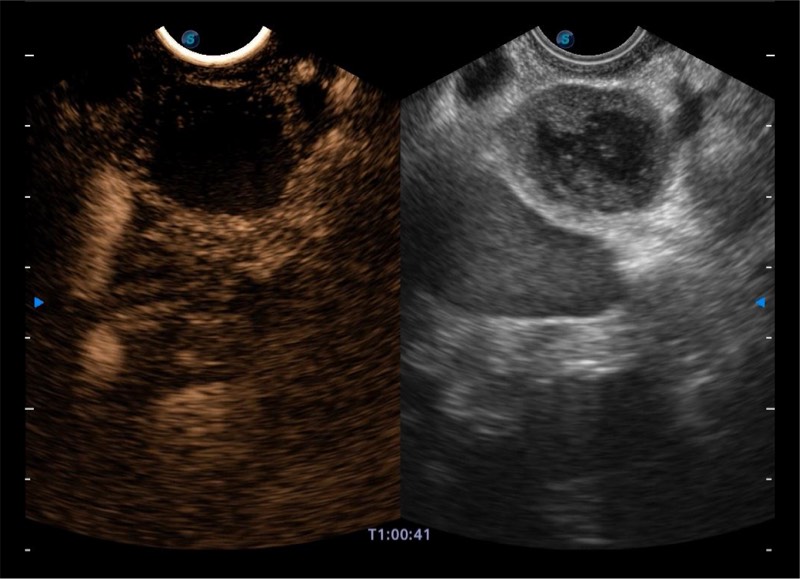

• 搭载百万级CMOS成像技术

• 及自主研发凸阵换能器,

• 可呈现优质的内镜和超声画面